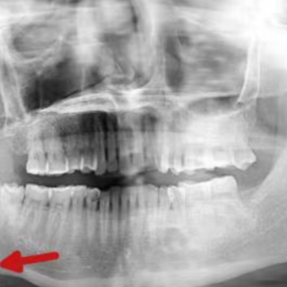

然而,近一个月来,肿痛日益加剧,且口底出现黄白色脓性渗出物,他这才急忙前往医院就诊。接诊医生龙静为谭先生完善检查后发现,他的口底竟藏着一颗约1.2厘米的“石头”,最终确诊为颌下腺导管结石。入院后,谭先生接受了全麻下“颌下腺切除术+颌下腺导管结石取出术”,目前术后恢复良好,已顺利出院。

好好的口腔里为什么会凭空长结石?这到底是种什么病?广东医科大学附属东莞松山湖中心医院(东莞市松山湖中心医院)口腔颌面外科主任医师姜刚勇为大家解答。